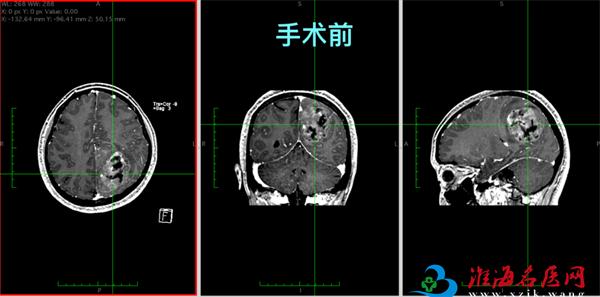

近日,徐州市中心医院神经外科董楠博士团队成功完成一例高风险脑肿瘤切除术。患者术后复查显示,肿瘤实现肉眼全切,颅内重要血管保存完好,手术区域无渗血,患者肢体活动障碍得到明显缓解,目前已康复出院。

术后患者行颅脑MRI复查,结果显示肿瘤实现肉眼全切,中央前回区域得到良好保护,上矢状窦等重要血管结构保存完好,手术区域未见明确渗血或血肿形成。患者术前存在的下肢活动障碍得到有效缓解,力量恢复正常,目前已康复出院,准备接受后续治疗。